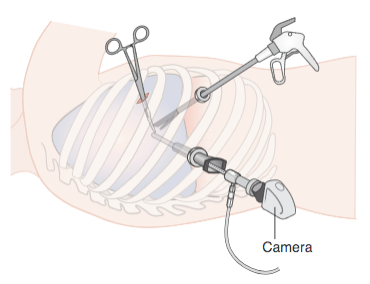

14/Imaging of trapped lung will typically show pleural thickening and loculation. An air contrasted CT can be used to better visualize the visceral pleura rind or you can use direct visualization with video-assisted thoracoscopy. @ReenaHem @ERitterMD @VCURadRes @MarkZieglerMD

16/ Management of an asymptomatic trapped lung is NOT pleural drainage as the effusion will just re-accumulate. However, decortication of the visceral pleura rind with VATS is typically your treatment for symptomatic patients who are surgical candidates. @VCUIMClerkship